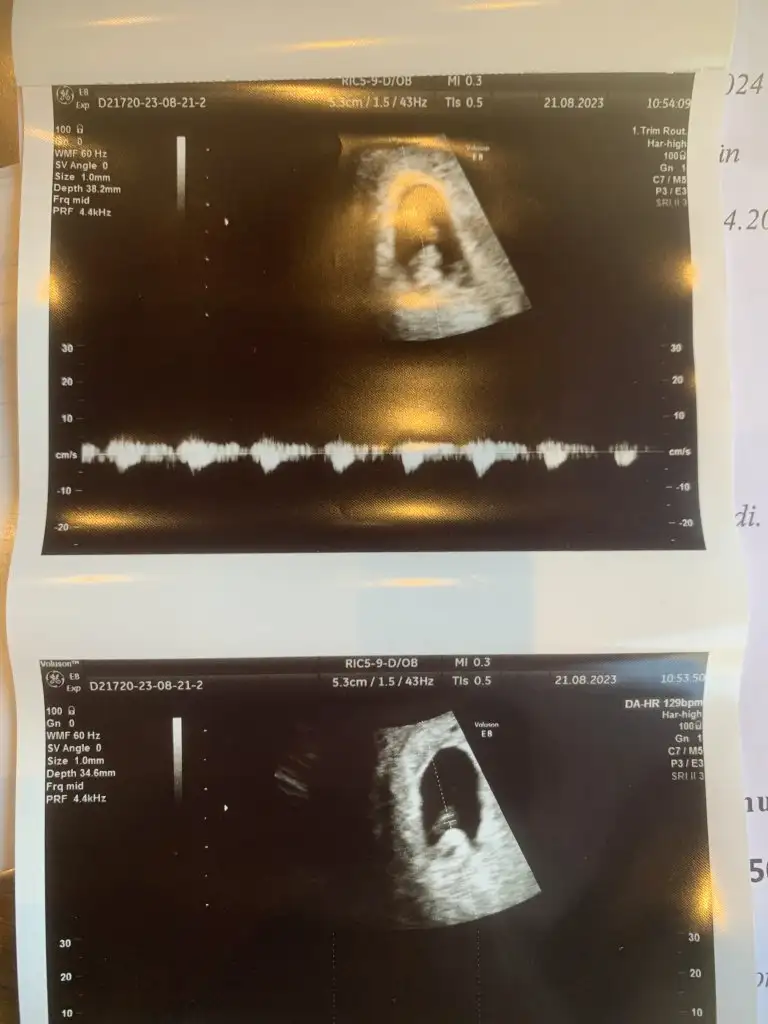

Kızlar merhaba🥰 rica etsem benim için de tahmin yapa bilirmisiniz? benimki ikizlerdi, birinin kalbi durdu 7 haftalıkken diğeri iyi , 9 hafta 1 gün , sizce bebeyim kız mı erkek mi ?

Eklentiler

• 65899116-5B80-4272-964C-B810E130E0E4.webp

65899116-5B80-4272-964C-B810E130E0E4.webp

21,9 KB · Görüntüleme: 309